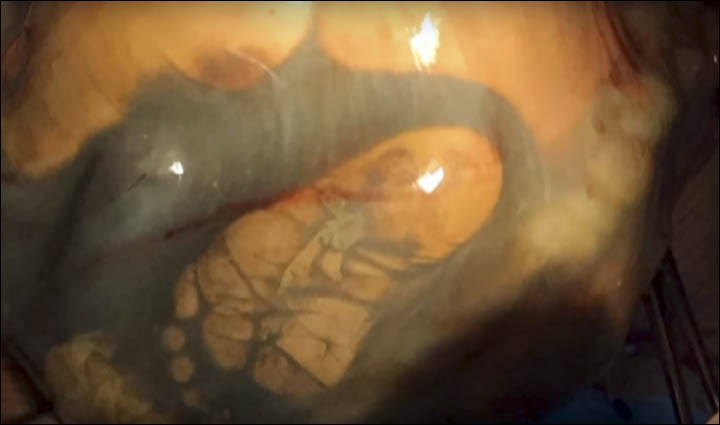

Wykonane prześwietlenie wykazało, że płód nie znajdował się w łonie, lecz w jamie brzusznej kobiety. Sam fakt, że udało mu się przetrwać całą ciążę, był absolutnie niesamowity.

W obliczu takiej sytuacji, jedynym rozwiązaniem był poród przez cesarskie cięcie. Nie było ono jednak bezpieczne. Wręcz przeciwnie, zabieg niósł za sobą  ogromne ryzyko, zarówno dla matki jak i dziecka.

Na szczęście, trwająca niemal dwie godziny operacja zakończyła się sukcesem. Lekarzom udało się uniknąć wywołania powikłań i dziewczynka przyszła na świat cała i zdrowa. Otrzymała ona imię Weronika.